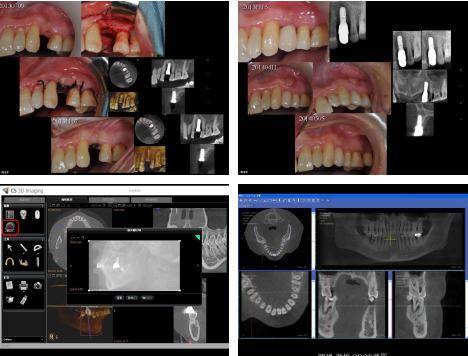

4. Пост-оперативна евалуација

Кључ за процену тачности имплантата је упоређивање грешке између симулиране позиције имплантата и стварне позиције имплантата, а кључ за процену је прикупљање информација о положају имплантата и израчунавање грешке у софтверу. .